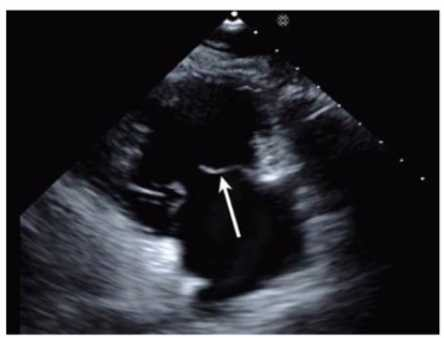

Which anatomic structure is represented by the arrow on this image?

1. Left leaflet

2. Posterior leaflet

3. Septal leaflet

4. Anterior leaflet

Answer(s): D

The echocardiographic image is a four-chamber view focusing on the mitral valve apparatus. The arrow points to the anterior leaflet of the mitral valve, which is typically more prominent, triangular in shape, and located adjacent to the aortic valve in the left ventricular outflow tract region.

The posterior leaflet of the mitral valve is generally smaller, has multiple scallops, and is located posteriorly relative to the anterior leaflet. The septal leaflet is part of the tricuspid valve on the right side of the heart. The "left leaflet" is a non-specific term and not an anatomical descriptor.

This differentiation between anterior and posterior leaflets is important for understanding mitral valve pathology and for interventions such as mitral valve repair. These features are clearly explained